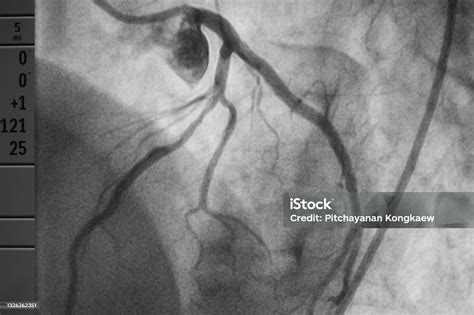

Aneurisma de arteria coronaria en la enfermedad de Kawasaki.